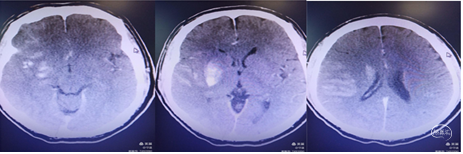

术后CT检查:造影剂外渗。

术后8小时出现意识不清,CT示脑水肿明显,给予去骨辨减压重症监护笫3天呈浅昏迷,双下肢肌力3级。第5天,病情加重,预后不良。

患者出现意识不清,病情加重。查CT左侧大脑中动脉区域水肿,低密度改变,中线移位。为大脑中动脉闭塞后改变,恶性脑水肿。

重症脑血管病管理:经甘露醇、白蛋白、3%氯化钠脱水、高压氧、依达拉奉、吡拉西坦脑保护治疗13天水肿消退,脑中线无移位,左侧大脑中动脉区域较前变淡。脑沟脑回显示清楚。